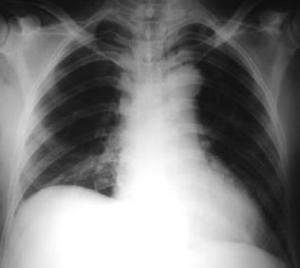

Torax PA:

A las 48 horas pos-operatorio, cumplió las condiciones para retirar el tubo torácico de expansión pulmonar y drenaje plaural.

Egresa al 5to. día pos operatorio, deambulando con control por neurocirugía, cirugía del tórax y medicina física y rehabilitación.